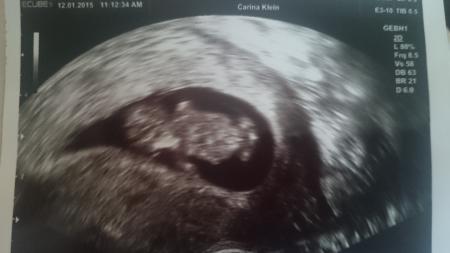

So bin wieder daheim :) Ich bin so erleichtert alles gut und so entwickelt wie es sein sollte. 3,4 cm vom Kopf bis Po *__* habe auch gleich 2 Bilder bekommen die hab ich angehangen nächster Termin ist dann am 9.02 wieder und dann ist endlich alles schlimme überstanden und ich kann mich freuen :D Auf dem einen Bild sind das nur die Füße und der Kopf auf dem anderen dann das ganze Gummibärchen *__*

Bild zu 3. US heute *__* - Forum für August - Mamis